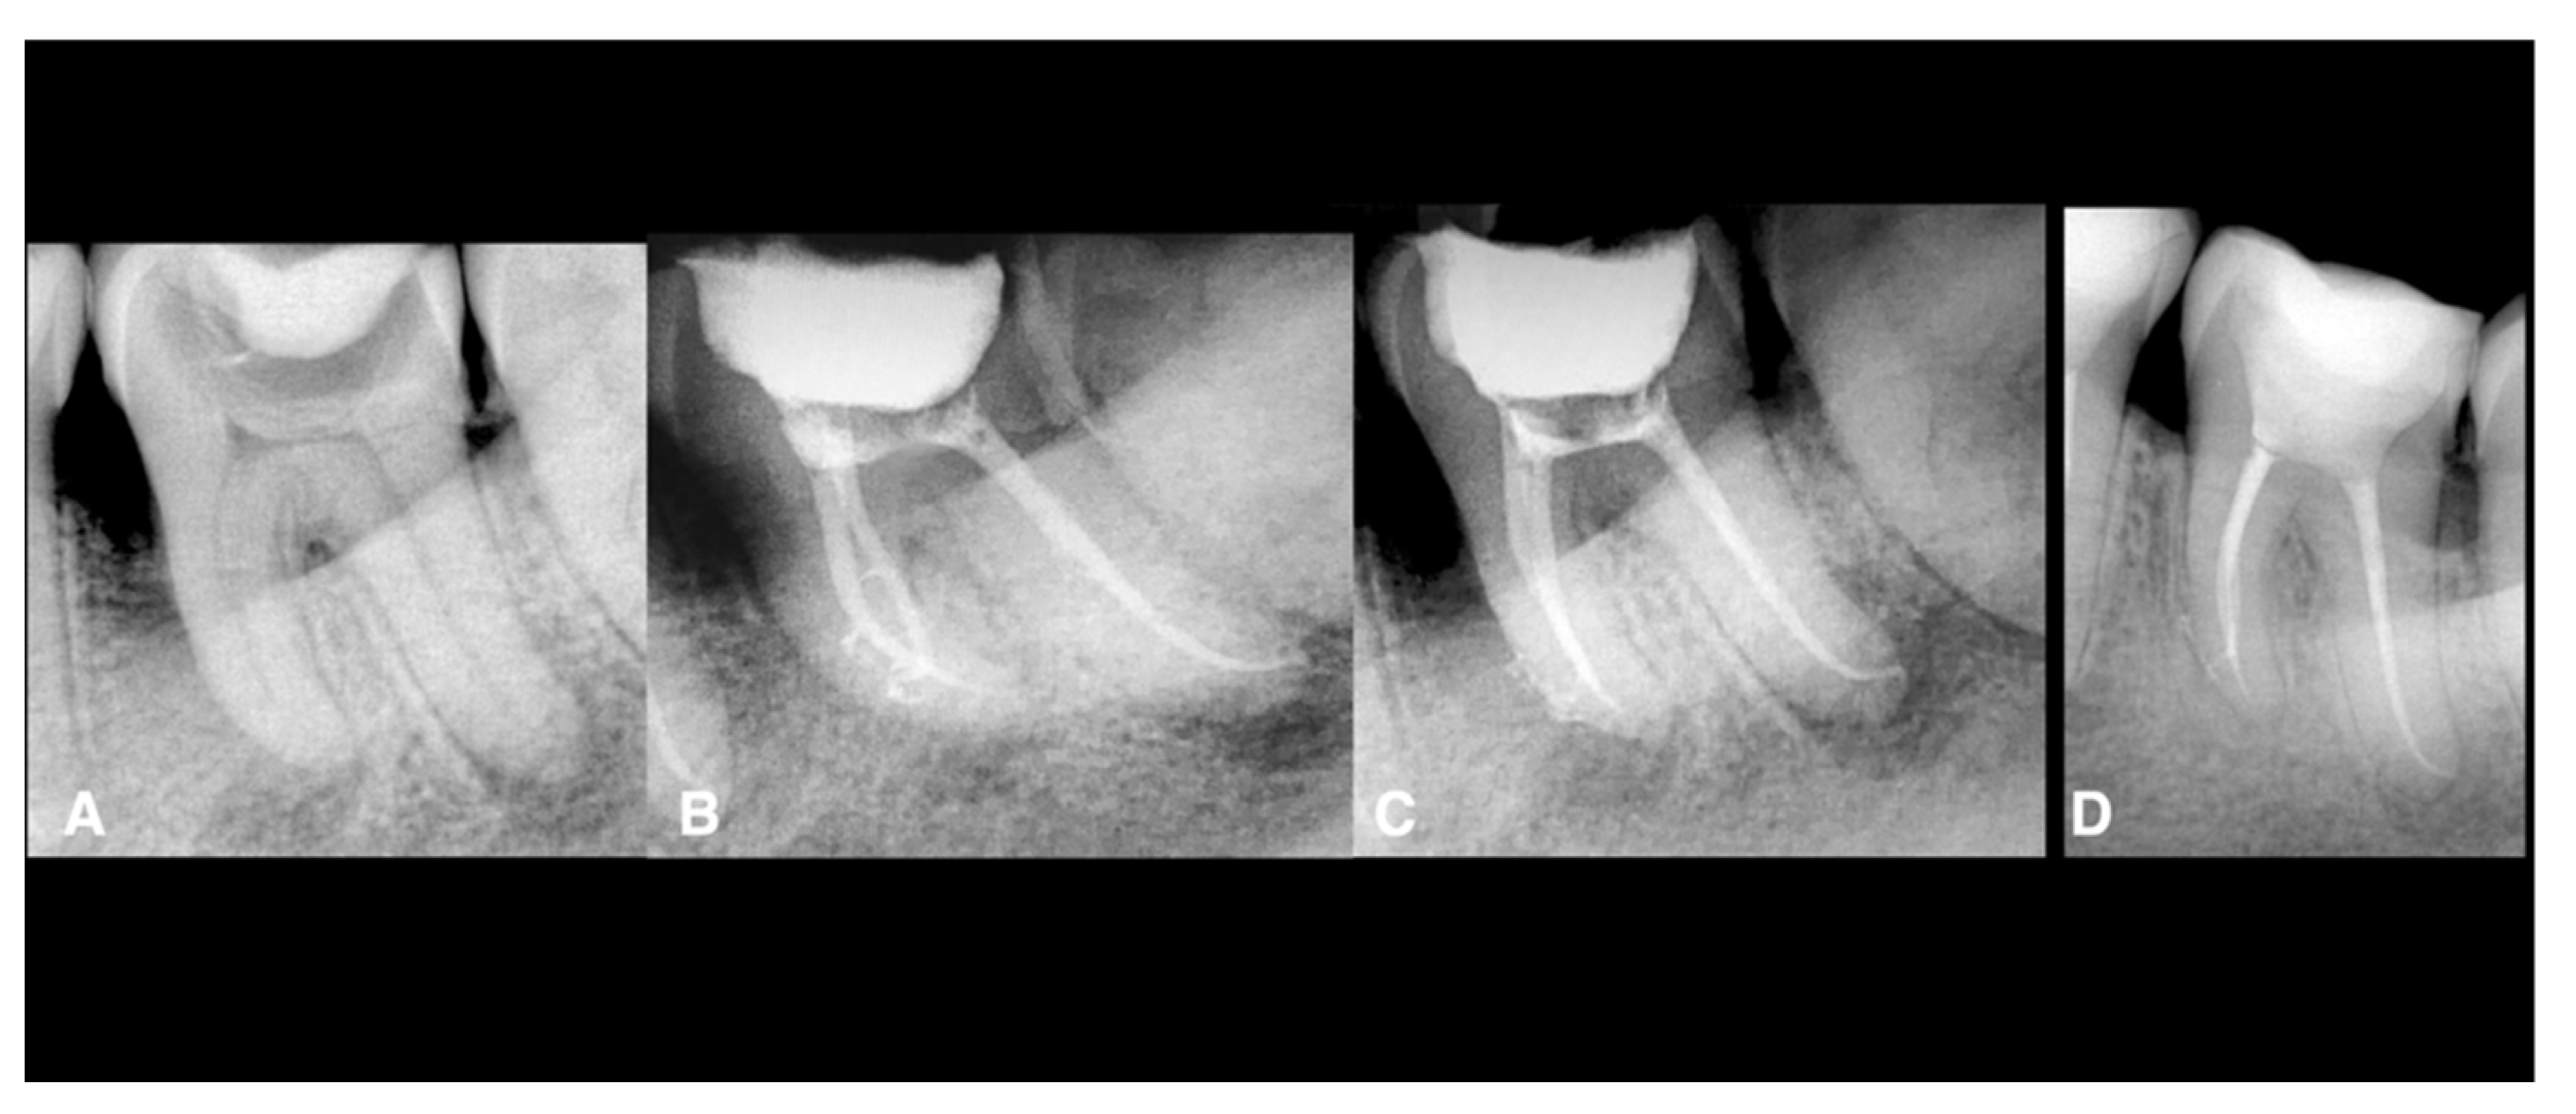

| All data Male: 55 Female: 35 Age: all the patients were between 20 and 45 years. Oral hygiene: 65 patients had good hygiene. Tobacco use: 10 patients used it. Teeth: 20 maxillary molars, 40 mandibular molars, 30 maxillary premolars. Intraoperative data collection Twenty teeth had sealer extrusions. The working length was respected in all teeth. Postoperative data collection Post-treatment symptoms were assessed two days after the treatment using a visual analogue scale (VAS; 0 and 10) Thirteen maxillary molars: 2 Seven maxillary molars: 1 Five mandibular molars: 4 Eighteen mandibular molars: 3 Ten mandibular molars: 2 Seven mandibular molars: 1 Sixteen maxillary premolars: 2 Twelve maxillary premolars: 1 Two maxillary premolars: 3 Total number: 90 teeth Two patients (2 teeth) did not come for the follow-up. Of the 88 teeth, 84 (95%) were healed, and four (5%) failed. Four teeth failed: 2 maxillary premolars and two mandibular molars (these teeth did not have sealer extrusion). One maxillary premolar failed with vertical root fracture. |